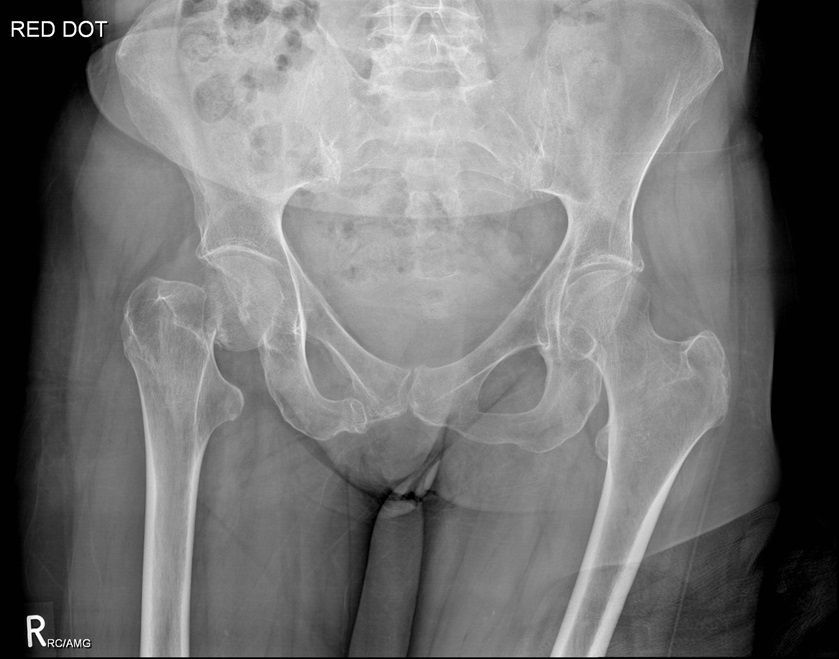

Question 2

Question

Which operation would you perform?

Answer

• THR

• Hemiarthroplasty